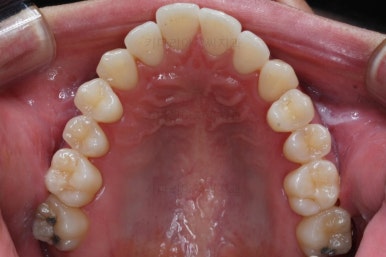

부산비수술교정 키다리아저씨치과에서 시행한 이번 치료의 결과입니다.

아랫니 갯수가 모자라고 중앙이 맞지 않았고 짝이 안맞는 상황이었으나 비교적 잘 마무리를 했어요.

거꾸로 물리는 상황이 개선되었기 때문에 앞니나 어금니의 교합은 이전과 비교할 수 없을만큼 좋아졌지요.